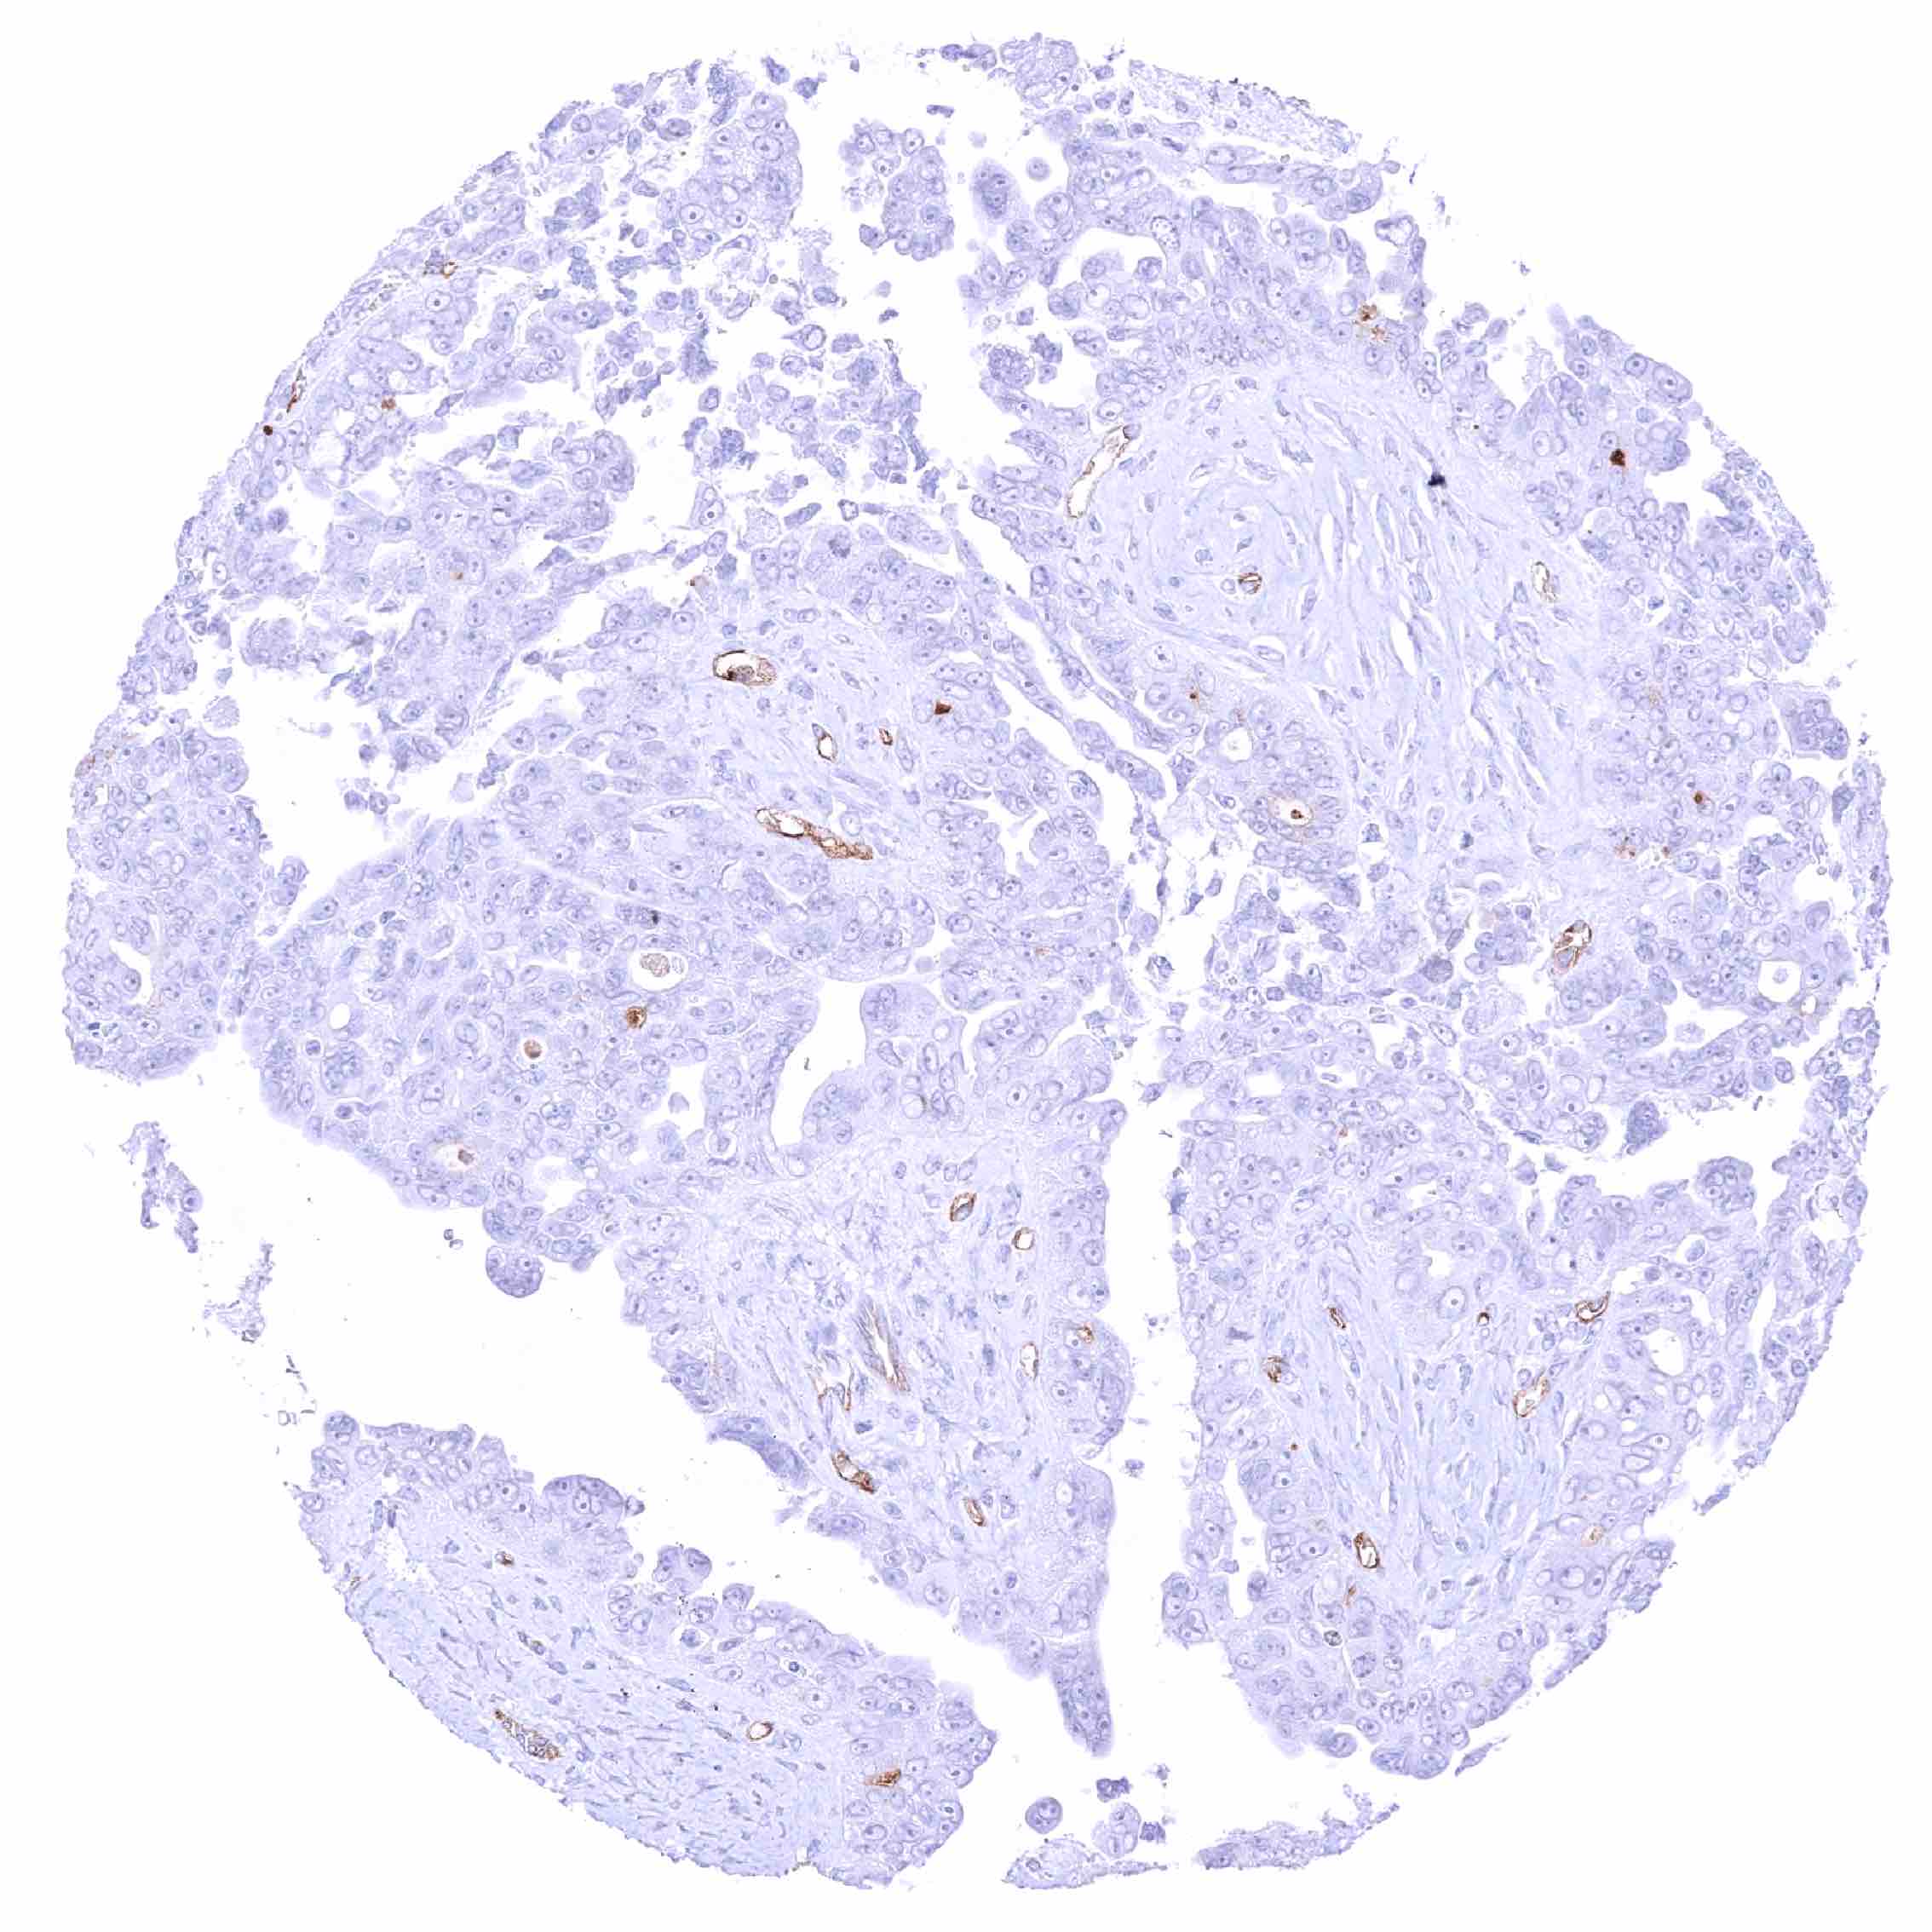

Urinary bladder – PODXL negative muscle-invasive urothelial carcinoma. Distinct PODXL positivity of endothelial cells of few vessels.